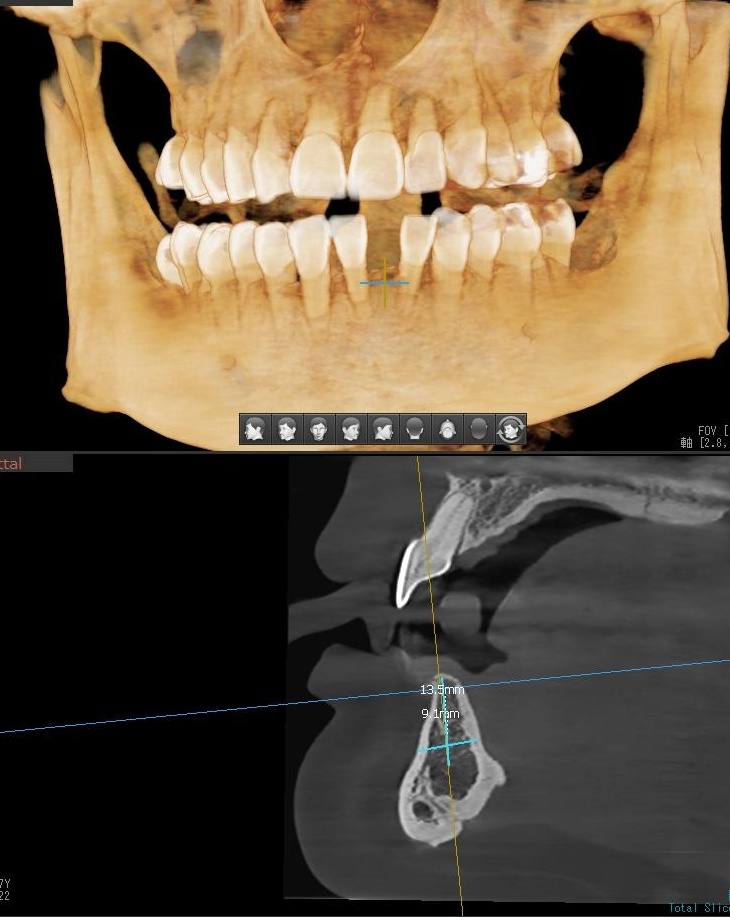

今回の患者様は先天的に欠損している右下1番目、左下1番目にインプラント植立を希望されました。

スペースが狭いため、今回の植立は1本に決まりました。

ドリルの先端を細い物から徐々に大きい物に変えながら、植立するインプラント体のネジの部分を除いた胴の部分の太さに合わせた大きさの穴を開けていきます。

開けた穴に、専用道具を使ってネジを締めるように長さ2センチ程のインプラントを骨に埋め込んでいきます。